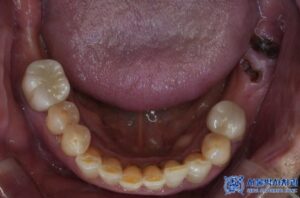

치료 마무리 후 사진입니다.

최종 보철물 세팅 이후 환자분께서는 불편함도 없었고,

교합 체크를 위해 다시 내원하셨을 때도

“음식 씹을 때 너무 편하고, 교합도 잘 맞는다”고

만족해하셨습니다.